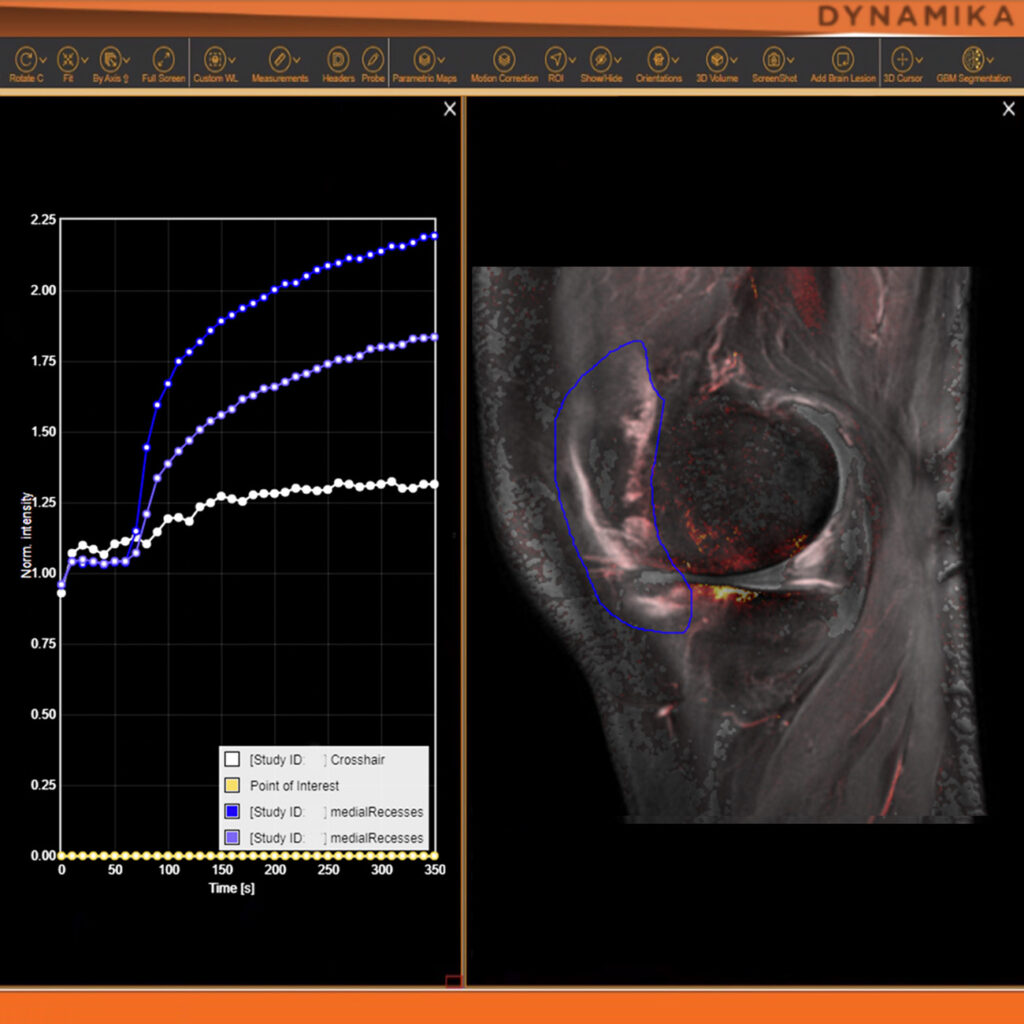

As an example, IAG was contacted by the USA based global pharmaceutical company to support their phase II clinical trial. The objective was to collect DCE-MRI scans from globally distributed sites and assess their drug for efficacy. Dynamic Contrast Enhanced MRI was used to assess the inflammatory changes.

The work involving 60 patients, which were analysed with IAG’s proprietary analysis technique showing that in this trial of patients with osteoarthritis, significant improvement in sub-clinical, synovial-based inflammation after 6 months of therapy was detected with this novel MRI-based quantitative tool.

Transparency: DYNAMIKA is a proprietary, secure image transfer and processing system that provides real-time access to tracking information throughout the study.

Managing data across multiple sites in clinical trials can be complex and time-consuming. Recognizing this challenge, our team of experts developed DYNAMIKA. It is IAG’s proprietary enterprise-scale cloud-based platform for imaging processing and data management. It works across multi-centre trial settings to enable central imaging review.​ This one comprehensive software system controls trial progress, conducts central reads and, when needed, it can be integrated with AI tools for earlier read-outs and decision support. Read more here.